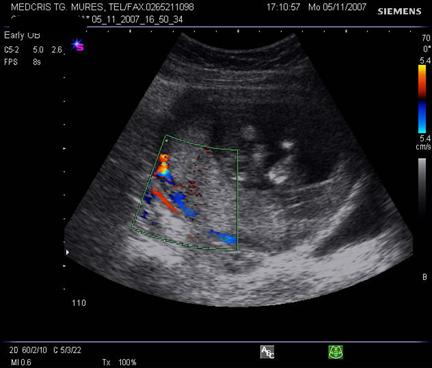

Fig. nr.222. Hematom

la nivelul placii deciduale a

placentatiei la 10 sapt. , cu intreruperea vascularizatiei la Doppler color (

sageata ). Se remarca vascularizatia cordonului ombilical si insertia centrala

a acestuia in placenta